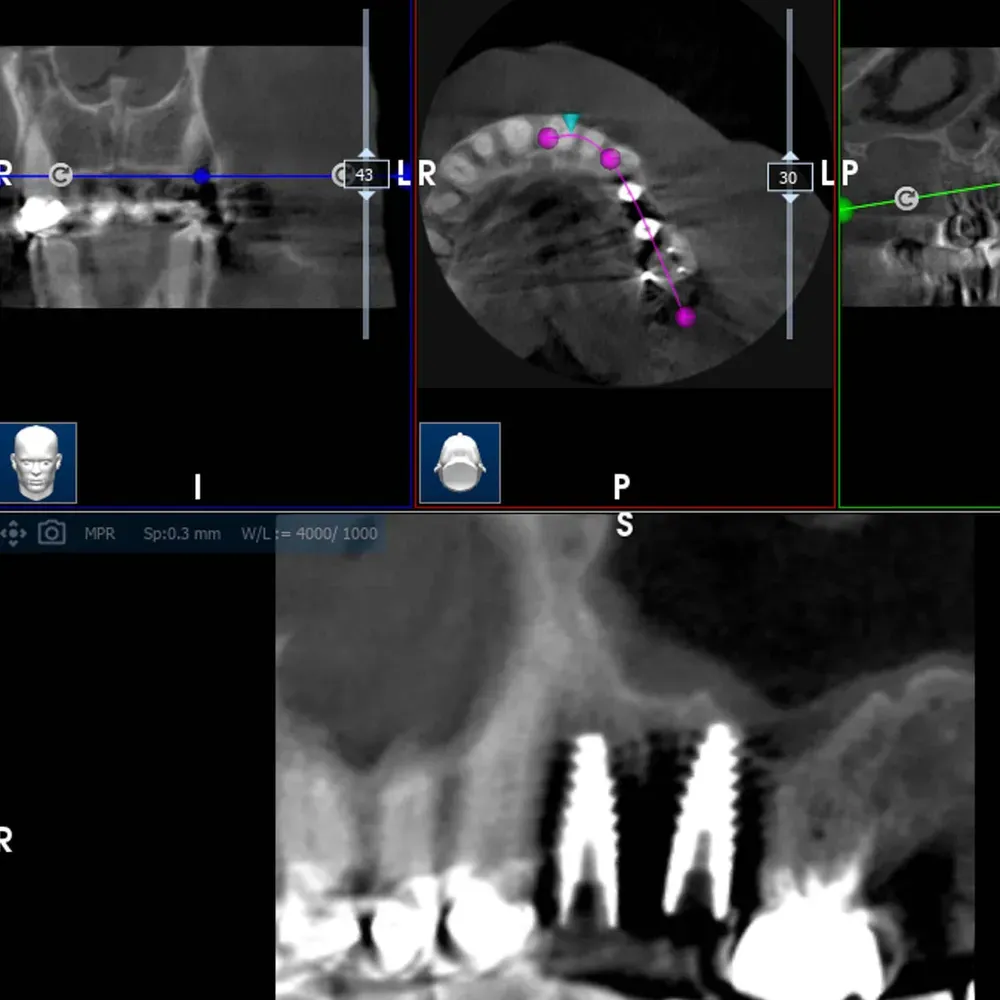

La CBCT intraoperatoria ha confermato la corretta posizione tridimensionale degli espansori e il raggiungimento della corticale del pavimento del seno in zona 2.5. In caso di dubbi sulla posizione e nel corso di interventi delicati come questo, questo ausilio strumentale è di fondamentale importanza. Ma non è sempre necessaria. L’esposizione, per quanto contenuta, dev’essere sempre ridotta al minimo, compatibilmente con la sicurezza chirurgica.

Sezione espansore sito 2.4

Sezione espansore sito 2.5

CBCT Post-op: Impianto in posizione 2.4 infracrestale che ha raggiunto la posizione di ingaggio corticale corretta

Espansore in posizione 2.5 con sollevamento della corticale del pavimento del seno

CBCT Post-op: Impianto in posizione 2.5 infracrestale con sollevamento della corticale del pavimento del seno